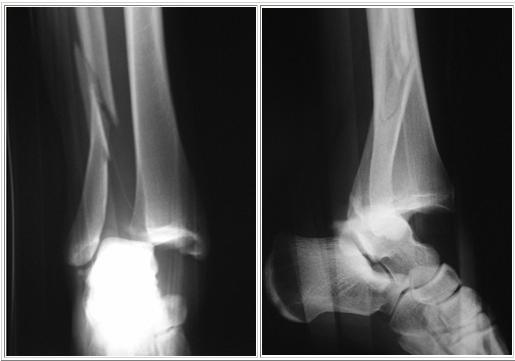

Patient consulte aux urgences pour douleurs importantes de cheville et impotence fonctionnelle après une chute. Des radios sont faites: quel diagnostic? Quel est le mécanisme lésionnel probable?

A

Fracture bimalléolaire de cheville sous-tuberculaire

mécanisme en aDduction forcée

Q

Quel est le diagnostic concernant la fracture de cheville sur cette radio? Quel est le mécanisme lésionnel probable?

Fracture bimalléolaire de cheville sus-tuberculaire

mécanisme en aBduction forcée